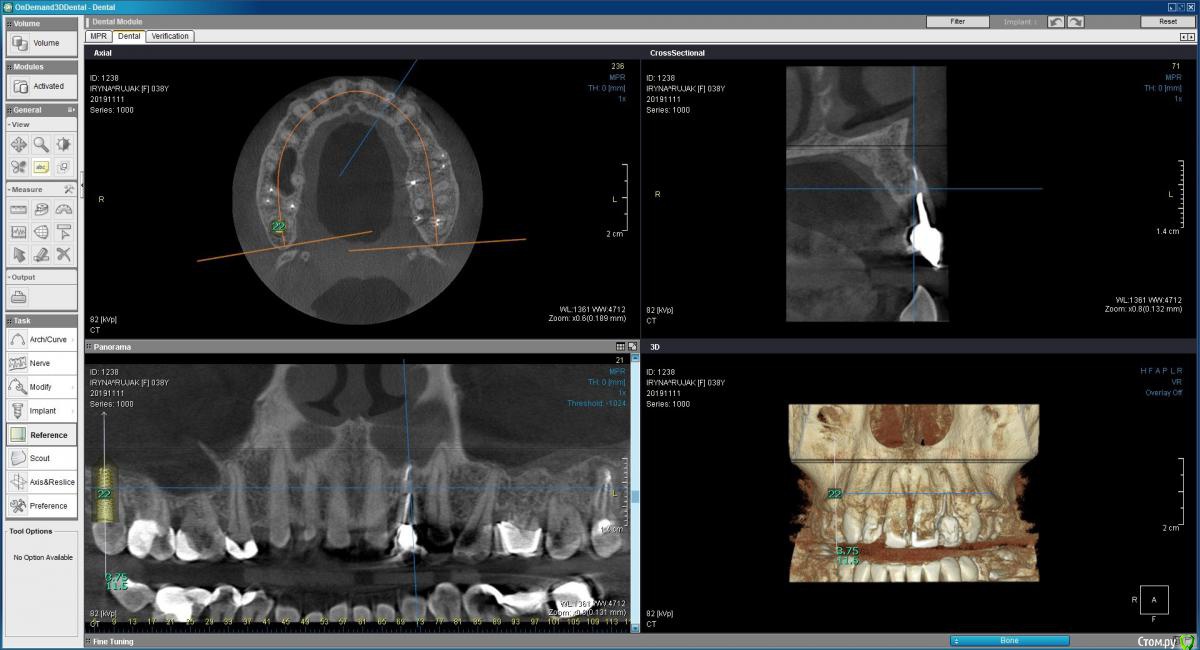

Пациентка 37 лет, не курит, соматически здорова. Частое выпадение ЛШКВ с коронкой. Диагностирована  фрактура вестибулярной стенки кореня зуба 22. Линия улыбки высокая. Биотип толстый.  Отсутствие вестибулярной пластинки, карман 8мм без ексудата.  Латеротрузия через 22.